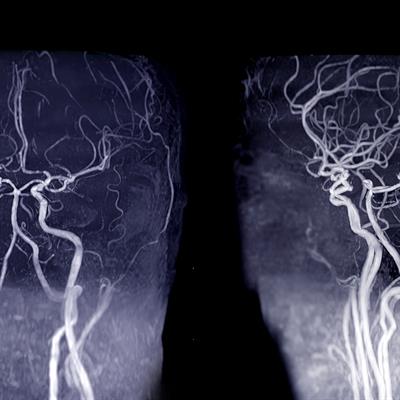

Distal, Medium Vessel Occlusion Stroke: Epidemiology, Diagnostics, Treatment Options, and Outcome Prediction